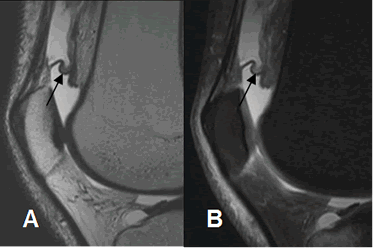

Fig 156. Plica suprapatelar.

A: RM sagital en T2 y B: RM sagital en STIR. Derrame articular con imagen serpentiginosa a nivel suprapatelar, que corresponde a plica.